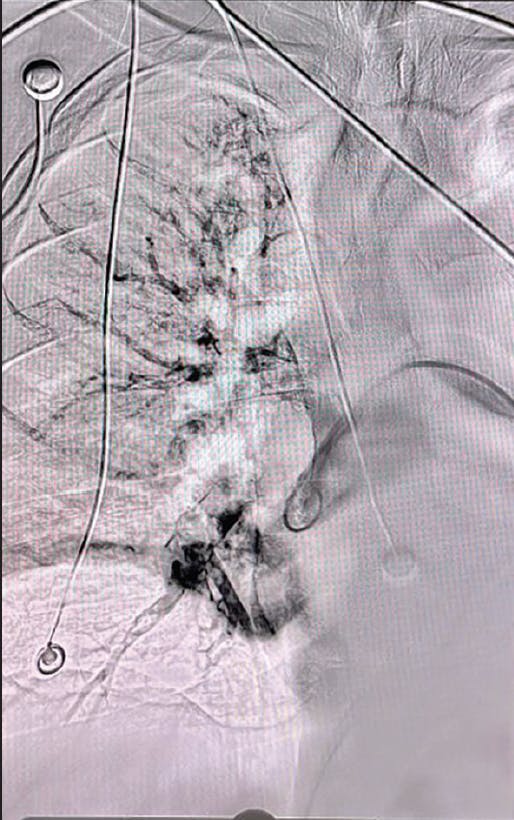

A patient in her early 60s presented with fatigue, sudden onset of sharp chest pain, and shortness of breath. Initial evaluation revealed resting tachycardia of 120 bpm with a BP of 93/80 mm Hg and an oxygen saturation of 84% on room air. Additionally, the patient had elevated troponin and BNP. A CT pulmonary angiogram (CTPA) revealed an extensive thrombotic burden involving all five lobes, with an elevated right ventricular/left ventricular (RV/LV) ratio of 1.3 (Figure 1). Parenteral anticoagulation was administered, and after discussion with the PE response team, she was transferred for advanced therapy. Based on the patient’s symptoms, the decision was made to pursue thrombus extraction with Lightning Flash due to the device’s moderate-bore profile and trackability.

Figure 1. Right and left initial angiograms.

INTERVENTION

Access was achieved in the right common femoral vein (CFV), and initial diagnostics revealed an elevated mean PA pressure of 34 mm Hg. After selection of the right lower lobar PA, the venotomy site was dilated over a wire and a 16-F, 33-cm Gore DrySeal sheath was placed. Under fluoroscopic guidance, a 16-F, 100-cm Lightning Flash XTORQ was advanced into the right PA and two passes were performed. Subsequently, the device was tracked into the left PA and two additional passes were performed. Figure 2 shows the amount of clot extracted. Reassessment of hemodynamics revealed improvement in mean PA pressure from 34 to 17 mm Hg, reflecting an on-table drop of 17 mm Hg. Additionally, selective bilateral pulmonary angiography showed significant improvement in perfusion (Figure 3). By the conclusion of the case, the patient was weaned from FiO2 of 15 L/min to room air.

Figure 2. Clot removed.

Figure 3. Post-thrombectomy right and left angiograms.

A patient in his late 50s presented to the emergency department (ED) with fatigue, shortness of breath, and emesis. The patient had previous medical history of hypertension, diabetes, and anemia. Initial diagnostics showed elevated levels of high-sensitivity troponin I at 482.8 ng/L, a HR of 104 bpm, and oxygen saturation of 91%. A transthoracic echocardiogram revealed mildly dilated RV size with mildly reduced ventricular systolic function. Evaluation of imaging and diagnostics confirmed a submassive saddle PE with right heart strain due to an RV/LV ratio of 1.9 (Figure 1, Figure 2, and Figure 3). The decision was made to pursue mechanical thrombectomy with Lightning Flash for the acute submassive PE.

Figure 1. CTPA showing a submassive saddle PE.

Figure 2. Initial angiogram.

Figure 3. Preprocedural venogram.

Access was obtained in the right femoral vein. The mean PA pressure before thrombectomy was 29 mm Hg. CTPA revealed acute bilateral PE in the bilateral lobar and main PAs (Figure 1). Thrombectomy was performed with the 16-F Lightning Flash device and resulted in < 50 mL of blood loss. A postprocedure pulmonary angiogram revealed successful mechanical thrombectomy with establishment of flow from the PAs to both lungs (Figure 4 and Figure 5). The patient’s HR decreased to 81 bpm, and his oxygen sats increased to 100%. The patient’s final high-sensitivity troponin I levels were measured at 123.8 ng/L. With a minimal 4-day hospital length of stay and no postprocedural complications, this PE procedure with Lightning Flash was successful.

Figure 4. Post-thrombectomy angiogram.

Figure 5. Clot removed.